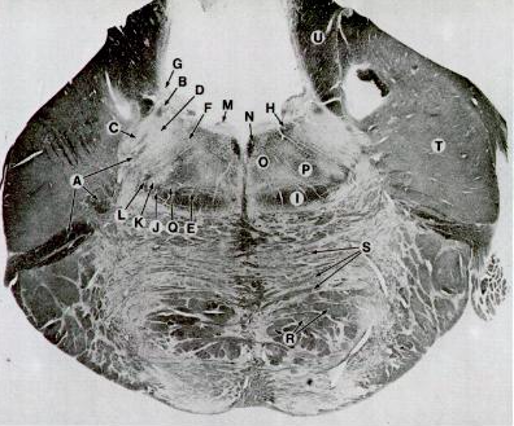

G

vestibular nuclei

S

pontocerebellar fibers

T

Middle cerebellar peduncle

R

Corticobrainstem

H

Facial nerve nucleus

N

MLF (Medial Longitudinal Fascilicus)

I

Medial Lemniscus

D

CrN. V Nucleus